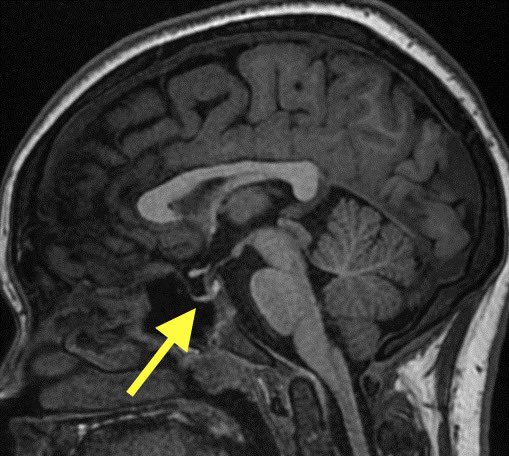

1️⃣Empty/partially empty sella: increased pressure results in forceful CSF pulsations which compresses the pituitary gland and empties the sella 🧠

1️⃣Empty/partially empty sella, just remember this is also a normal incidental finding of aging as years and years of CSF pulsations can cause a flattened pituitary gland

Therefore, in the absence of other findings or appropriate history I do not mention empty sella after ~ 45yrs